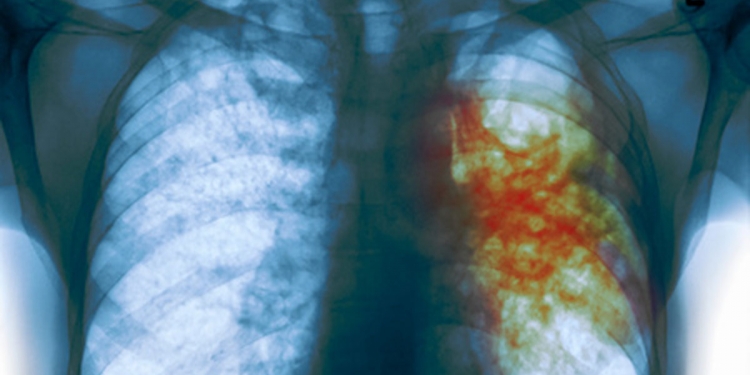

La tuberculosis es una enfermedad causada por Mycobacterium tuberculosis, una bacteria que casi siempre afecta a los pulmones. Es curable y prevenible. Se transmite de persona a persona a través del aire. Cuando un enfermo de tuberculosis pulmonar tose, estornuda o escupe, expulsa bacilos tuberculosos al aire. Basta con que una persona inhale unos pocos bacilos para quedar infectada.